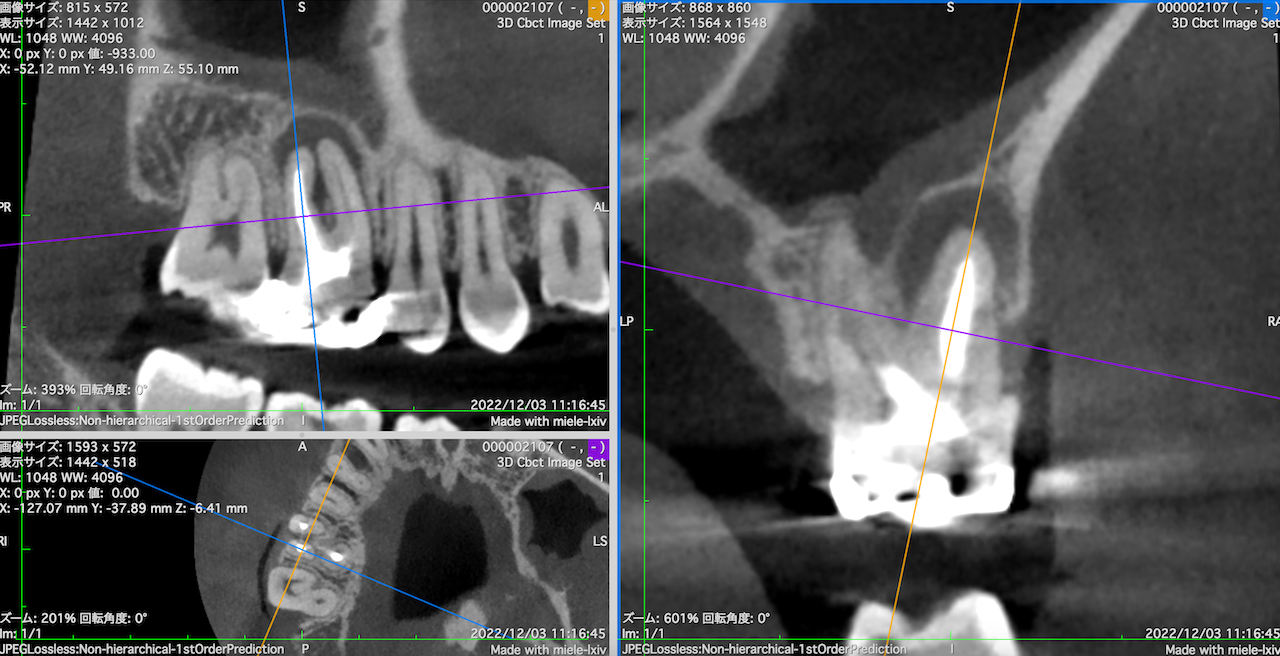

この流れで計測すると以下のようになる。

#3 MB

#3 DB

MBとDBは近接し、3mmで切断した際の頬舌的な厚みも3.5~4mmだ。

そしてMB1, MB2は近接している。

またMBもDBも近接している。

以上のことからこのApicoectomyは容易であると私にはわかる。

あなたにはそれがわかるだろうか?その理由を含めて、だ。